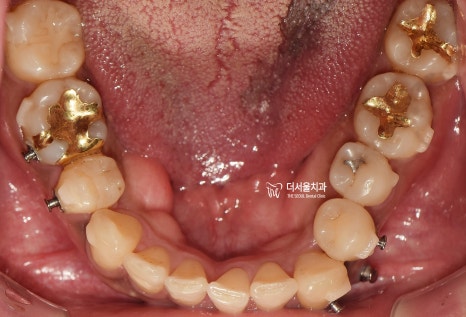

그러면서 하악에서도,

치열의 불규칙성이 같이 관찰되는데

결국 이런 치열들 때문에,

발치를 결정할 수 밖에 없었고

양측으로 동시에 발치를 하는게 아닌,

#14, 44번 치아만 발치하는

편측발치로 진행을 하게 될 상황입니다.